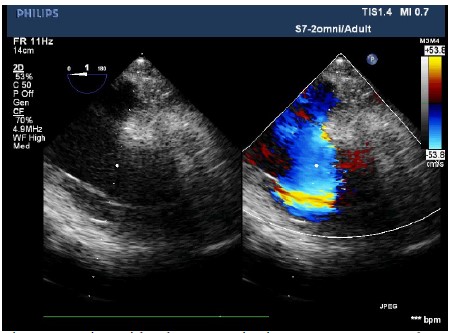

The patient entered the operating room and her ECG was monitored regularly. The induction of anesthesia was smooth. When the surgical team was manipulating the fracture, her blood pressure (BP) suddenly decreased to 63/43 mmHg, heart rate increased to 112 beats/min, and the saturation of pulse oxygen (SpO2) fell to 72%. 1 mg methoxamine was used to raise the blood pressure without success. 2 mg methoxamine, 6 mg ephedrine, and 8 μg nonadrenaline were subsequently given without significant blood pressure change. The central venous pressure was 15mmHg. In addition, the end tidal carbon dioxide decreased to 10 mmHg. There were no significant airway pressure changes. While an allergic reaction was initially suspected, no dermatological changes were identified. Emergency blood gas indicated a partial pressure of artery carbon dioxide (PaCO2) of 77.9 mmHg, and an oxygen partial pressure of 67mmHg. Potential pulmonary embolism was suspected. A transesophageal echocardiography (TEE) was followed. It revealed an enlarged right atrium (Figure1), hypokinesia of the free right ventricle wall, and poor filling of left ventricular. The ratio of left/right ventricular apparent disorder and the pressure of tricuspid valve was 51mmHg with massive regurgitation of 3.57m/s (Figure 2). Severe tricuspid reflux was also observed (Figure 3). Epinephrine and milrinone along with high-dose vasopressin were initiated. While no thrombi in the pulmonary or right ventricle were identified, unstable hemodynamics, changes in carbon dioxide, findings in TEE strongly suggested a possible major PE. Extracorporeal membrane oxygenation (ECMO) was immediately established and an emergent pulmonary thromboembolectomy was successfully performed. The patient was transferred to the surgical intensive care unit for monitoring and evaluation. The patient was discharged without residual deficits after 20 days in surgical intensive care unit.

Figure 2: An imaging of a 2D-transesophageal echocardiography shows tricuspid valve regurgitation with the speed of 3.57m/s and Tricuspid valve pressure of 51 mmHg.